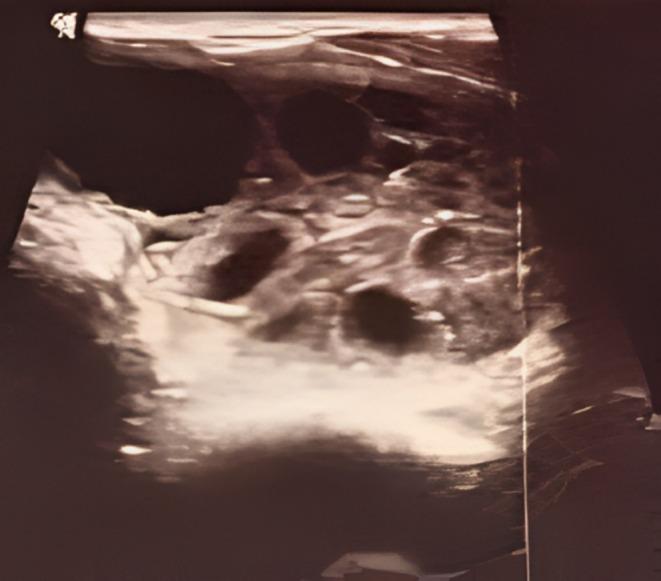

Hydatid cysts in the thyroid gland are extremely rare, even in endemic areas. A 64-year-old male presented with a painless swelling on the left side of the thyroid swelling for 2 years. Ultrasonography revealed a large multiloculated anechoic lesion while fine needle aspiration cytology yielded clear watery to granular fluid containing hooklets, protoscolioces, laminated membrane, identifiable on both Giemsa stained and unstained slides. Further tests confirmed positive serology for , and computed tomography (CT) scan showed no such cysts in other organs. The patient was treated successfully with a lobectomy without signs of recurrence in 1 year. Although primary hydatid cysts of the thyroid are rare, even in endemic areas, they should be considered as a differential diagnosis when evaluating thyroid nodules in these regions. Fine needle aspiration cytology (FNAC) can confirm the diagnosis. However, clinicians must take care to avoid anaphylactic reactions. The use of FNAC in hydatid disease is debatable as it may cause anaphylactic reaction, but in cases with doubtful diagnosis, it can serve as a confirmatory tool. The condition can be managed successfully with lobectomy.

甲状腺包虫囊肿极为罕见,即使在流行地区也是如此。一名64岁男性因甲状腺左侧无痛性肿胀就诊,病程2年。超声检查显示一个大的多房性无回声病变,细针穿刺细胞学检查抽出清亮水样至颗粒状液体,其中含有小钩、原头节、板层膜,在吉姆萨染色和未染色的玻片上均可识别。进一步检查证实血清学阳性,计算机断层扫描(CT)显示其他器官无此类囊肿。患者接受叶切除术治疗成功,1年内无复发迹象。尽管甲状腺原发性包虫囊肿罕见,即使在流行地区也是如此,但在评估这些地区的甲状腺结节时,应将其视为鉴别诊断之一。细针穿刺细胞学检查(FNAC)可确诊。然而,临床医生必须注意避免过敏反应。FNAC在包虫病中的应用存在争议,因为它可能引起过敏反应,但在诊断存疑的病例中,它可作为一种确诊工具。该疾病通过叶切除术可成功治疗。